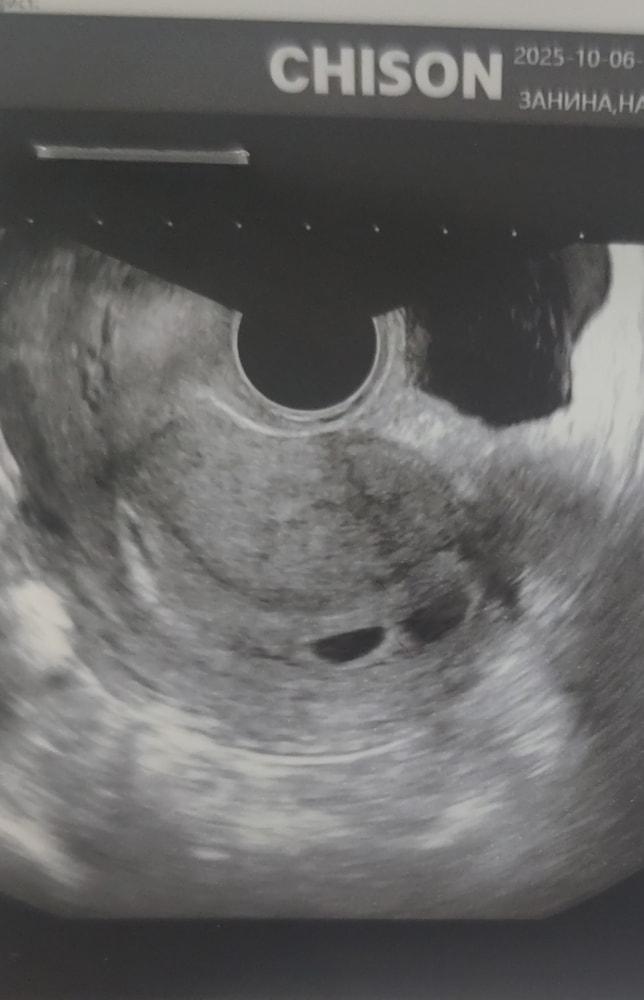

Через неделю пришла на УЗИ снова. Акушерский срок 6 недель -- ожидали увидеть эмбрион, но на экране только плодное яйцо. Узистка говорит: похоже, беременность не развивается. А потом приглядывается и находит по соседству ещё одно "пятнышко".

"То ли второе плодное яйцо, то ли скопление жидкости. Пока эмбрионов не видно, точно сказать не могу. Ставлю замершую под вопросом. Через 10 дней посмотрим, станет ясно" -- сказала мне узистка.

Я в шоке. То есть либо двойня, либо ни одного? И как вообще возможно, что в 5 недель был один, а в шесть стало два?

УЗИ 6 недель.